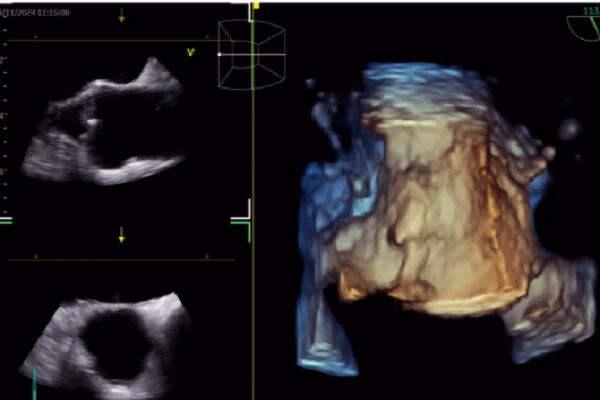

Theo bác sĩ Nhật, hình ảnh học tim mạch là một trong những lĩnh vực có nhiều nghiên cứu và ứng dụng AI nhất. Các công nghệ như điện tâm đồ (ECG), siêu âm tim, CT tim, MRI tim đang được tích hợp với AI để mang lại kết quả chẩn đoán chính xác hơn. AI được ứng dụng trong ECG để dự đoán các bệnh lý như rung nhĩ, suy tim có phân suất tống máu giảm và hẹp van động mạch chủ. Trong siêu âm tim, AI giúp nhận diện cấu trúc cơ tim, đo đạc tự động và hỗ trợ báo cáo và chẩn đoán.